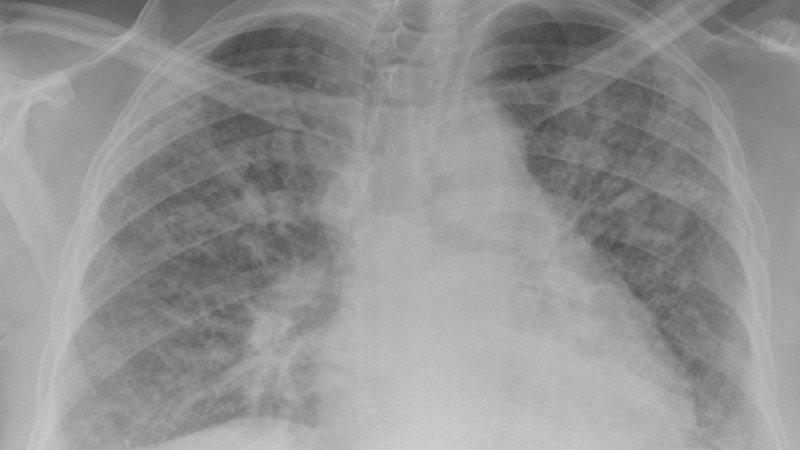

Xơ phổi là một căn bệnh mạn tính nguy hiểm, đặc trưng bởi sự hình thành các mô sẹo trong phổi, làm suy giảm nghiêm trọng chức năng hô hấp. Cách điều trị xơ phổi không chỉ tập trung vào việc làm chậm tiến triển của bệnh mà còn cải thiện chất lượng cuộc sống cho người bệnh.

Bệnh xơ phổi là một căn bệnh gây ra nhiều khó khăn và ảnh hưởng đến đời sống của bệnh nhân. Việc điều trị đòi hỏi một chiến lược điều trị đa chiều, kết hợp nhiều phương pháp khác nhau. Mỗi phương pháp điều trị đều đóng vai trò quan trọng trong việc quản lý và kiểm soát các triệu chứng của bệnh.